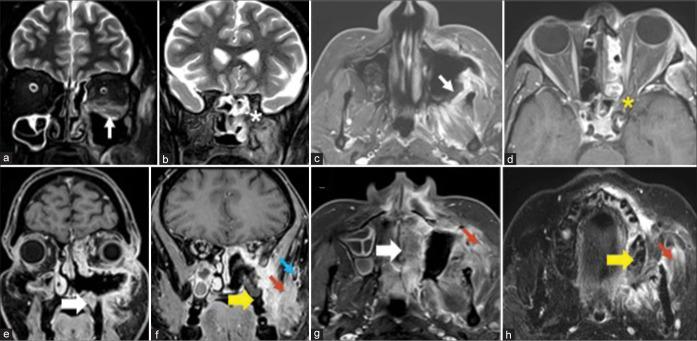

The most frequent MRI finding was T2 hypointensity in the sinonasal mucosa (94%) followed by mucosal necrosis/loss of contrast-enhancement (92.6%). Extrasinosal inflammation with or without necrosis in the pre-antral fat, retroantral fat, pterygopalatine fossa, and masticator space was seen in 91.1% of the cases. Extrasinosal spread was identified on MRI even when the computed tomography (CT) showed intact bone with normal extrasinosal density. Orbital involvement (72%) was in the form of contiguous spread from either the ethmoid or maxillary sinuses; the most frequent presentation being orbital cellulitis and necrosis, with some cases showing extension to the orbital apex (41%) and inflammation of the optic nerve (32%). A total of 22 patients showed involvement of the cavernous sinuses out of which 10 had sinus thrombosis and five patients had cavernous internal carotid artery involvement. Intracranial extension was seen both in the form of contiguous spread to the pachymeninges over the frontal and temporal lobes (25%) and intra-axial involvement in the form of cerebritis, abscesses, and infarcts (8.8%). Areas of blooming on SWI were noted within the areas of cerebritis and infarcts. Perineural spread of inflammation was seen along the mandibular nerves across foramen ovale in five patients and from the cisternal segment of trigeminal nerve to the root exit zone in pons in three patients. During follow-up, patients with disease progression showed involvement of the bones of skull base, osteomyelitis of the palate, alveolar process of maxilla, and zygoma. Persistent hyperenhancement in the post-operative bed after surgical debridement and resection was noted even in patients with stable disease.

Contrast-enhanced MRI must be performed in all patients with suspected AIFRS as non-contrast MRI fails to demonstrate tissue necrosis and CT fails to demonstrate extrasinosal disease across intact bony walls. Orbital apex, pterygopalatine fossa, and the cavernous sinuses form important pathways for disease spread to the skull base and intracranial compartment. While cerebritis, intracranial abscesses, and infarcts can be seen early in the disease due to the angioinvasive nature, perineural spread and skull base infiltration are seen 3-4 weeks after disease onset. Exaggerated soft-tissue enhancement in the post-operative bed after debridement can be a normal finding and must not be interpreted as disease progression.